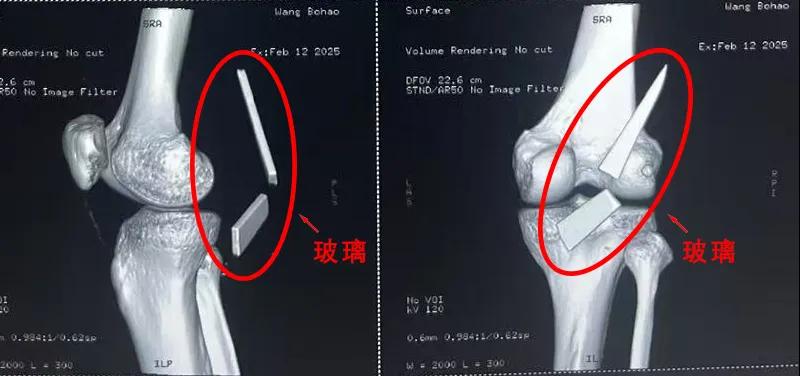

13厘米碎玻璃扎入腿中,漯河醫(yī)專二附院顯微外科緊急“拆彈”......

“兩塊碎玻璃加起來(lái)有13cm長(zhǎng),這要是傷到了血管,后果可是不敢設(shè)想......”雖然手術(shù)已經(jīng)順利結(jié)束,回憶起當(dāng)時(shí)的畫(huà)面,患者家屬還是心有余悸。

患者家屬這才開(kāi)始意識(shí)到問(wèn)題的嚴(yán)重性,便帶著孩子到鄉(xiāng)鎮(zhèn)衛(wèi)生院檢查——結(jié)果顯示右膝關(guān)節(jié)后方竟然殘留著兩塊兒鋒利的碎玻璃,測(cè)量后預(yù)估玻璃總長(zhǎng)將近13厘米!

由于玻璃位置毗鄰坐骨神經(jīng)和股動(dòng)脈,一旦刺破股動(dòng)脈,將嚴(yán)重威脅生命。家屬著急萬(wàn)分,想著能否盡快手術(shù)取出碎片,于是慕名來(lái)到漯河醫(yī)專二附院(漯河市骨科醫(yī)院、漯河市立醫(yī)院)手顯微外科(修復(fù)重建骨感染科)。

術(shù)中,馬廣輝醫(yī)生憑借扎實(shí)的理論知識(shí)和嫻熟的顯微外科技術(shù),順利找到深深刺進(jìn)肌肉的兩塊玻璃,肉眼可見(jiàn)玻璃尖端距股動(dòng)脈僅有不到半公分的距離!如果患者再耽誤半天或者再多活動(dòng)幾次膝關(guān)節(jié),小指粗的股動(dòng)脈很有可能被玻璃扎破,后果難以想象。

最終,馬廣輝醫(yī)生在血管、神經(jīng)表面順利取出兩塊玻璃碎片,拆除了埋在患者膝關(guān)節(jié)的“炸彈”。在告知患者家屬術(shù)中情況后,家屬懸著的心終于放了下來(lái)。